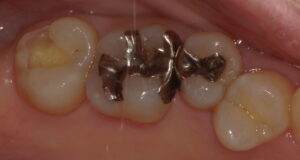

おそらく術前の保険診療では2,3分で詰めたと思いますが、今回この歯は防湿から精密充填まで20分ほどかかっております。